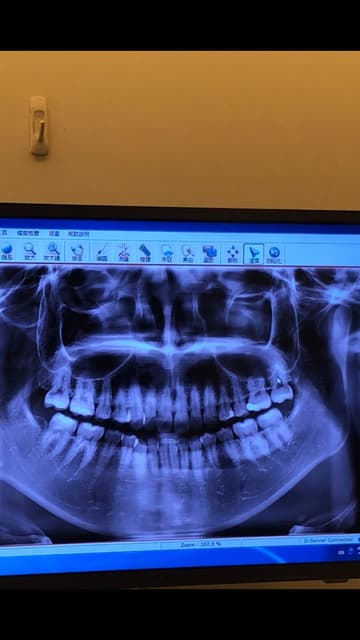

智齿长歪dcard-Jun 05, 19 · 智齿长歪怎么处理?:这种情况通过x线检查,判断应该是复杂型智齿牙根,如果拔牙会有一些难度,容易出现牙根残留等问题。 因此往往需要先静脉注射抗生素预防感染23?Mar 31, 15 · 智齿长歪了,经常发炎的同学还是要去拔了它的,一了百了。 对了,weibo上那个视频是真的是这样的,麻药,切开,撬,敲,样样上阵。(我是要这样啦。当然也有一些体质好的同学,一下子就拔出来,不用那么麻烦的。) 其他拔完之后牙齿也会教的了。乖乖

智齿长歪了一定要拔掉吗 百度知道

智齿长歪了一定要拔掉吗